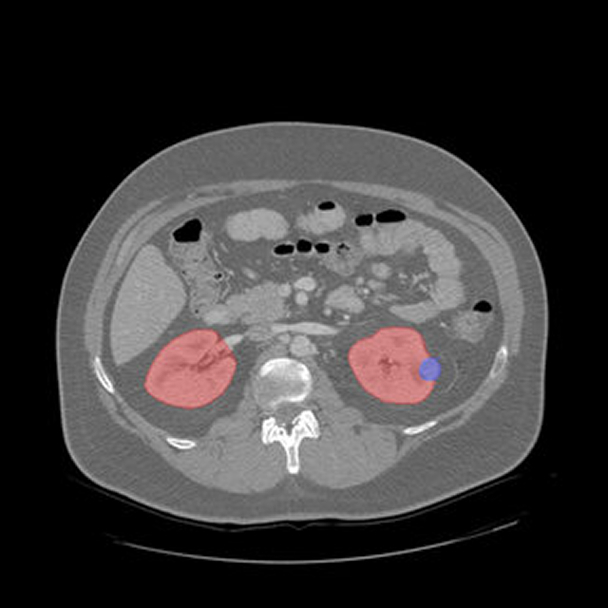

3D image segmentation is revolutionizing the way clinicians and researchers understand the human body. By transforming 2D medical images into precise 3D models, this technology enables deeper anatomical insights, enhances diagnostic accuracy, and streamlines surgical planning. At the forefront of AI-driven healthcare innovation, segmentation serves as the foundation for effective treatment, data-driven decisions, and scalable clinical research.

3D image segmentation, a technique that isolates anatomical regions from MRI, CT, or ultrasound, is foundational in clinical diagnosis, treatment planning, and quantitative analysis. When applied in 3D, it enables:

- Quantitative analysis through volumetric measurements of organs or lesions is crucial for tracking disease progression and therapy effectiveness.

- We combine clinician expertise and advanced annotation tools to efficiently annotate 3D medical volumes, cutting annotation labor while preserving accuracy.